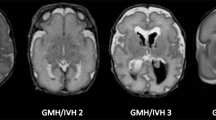

Term infants (control), premature infants without (normotypic) and with perinatal HIE (HIE) underwent brain magnetic resonance imaging at term-equivalent age (TEA) and at 2 years. Cerebrum, cerebellum, brainstem divisions and ventrodorsal compartments volumetric analysis were performed, as well as fractional anisotropy (FA) and apparent diffusion coefficient (ADC) of corticopontine, corticospinal pathways and middle cerebellar peduncles. Amiel-Tison scale at TEA and the Hempel test at 2 years were assessed.

Cerebellum, brainstem and its compartments volumes were decreased in normotypic and HIE groups at TEA, while at 2 years volumes were significantly reduced in the HIE group, accompanied by decreased volume and FA and increased ADC of corticopontine and corticospinal pathways. Negative association of the brainstem, cerebellum, mesencephalon, pons, corticopontine volumes and corticospinal pathway FA at TEA with the neurological score at 2 years. Cerebellum and pons volumes presented as potential prognostic indicators of neurological outcomes.